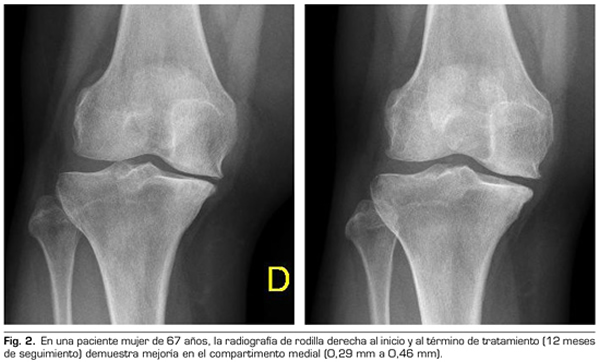

Con respecto a las variables radiológicas, al valorar a 53 de los 115 pacientes que cumplieron un año de seguimiento después del tratamiento con ozono, se observó que el compartimento interno aumento significativamente de 4,12 ± 1,41 mm a 4,4 ± 1,35 mm (p = 0,0008) y el compartimento externo aumentó de 6 ± 1,37 a 6,16 ± 1,4 mm (p = 0,0753) (Tabla II). Se presentan 2 casos clínicos como muestra del cambio radiológico en los compartimentos interno y externo (Figuras 2 y 3).

Tras un año de seguimiento con controles radio-lógicos a 53 de los 115 pacientes del estudio, el ozono (O2-O3) ha sido capaz de aumentar el mínimo espacio articular del compartimento medial (de 4,12 a 4,44 mm) y del compartimento lateral (de 6,0 a 6,16 mm), revirtiendo la artrosis de rodilla en nuestra serie de casos. Este hallazgo sugiere el efecto modificador de la enfermedad del ozono (O2-O3) sobre la artrosis de rodilla, hallazgos que coinciden con lo reportado recientemente por Fernández-Cuadros y cols. (9).